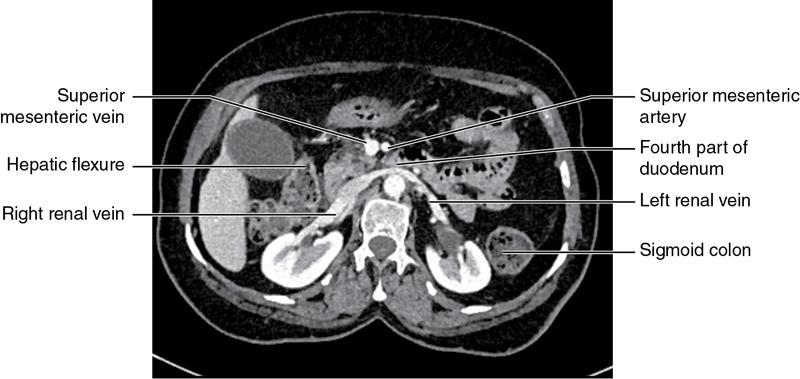

CROSS SECTIONAL ANATOMY OF ABDOMEN Satya Jha NORMAL ANATOMY OF ABDOMEN AND PELVIS Amandeep Singh The two major surfaces: The anterior and posterior layers of the coronary ligament converge on bare area (not covered by peritoneum). Its right and left margins form the right and left triangular ligaments. The right triangular ligament extends toward the diaphragm and separates right subphrenic space from right subhepatic space. The left triangular ligament gives tracts extending to the diaphragm and falciform ligament and does not compartmentalize the left subphrenic space. Ligamentum teres or the obliterated umblical vein is contained in falciform ligament which attaches the liver to anterior abdominal wall. The main portal vein, the proper hepatic artery and the common bile duct are contained within investing peritoneal folds of hepatoduodenal ligament at the porta hepatis (Fig. 7.2.2.1). Liver is divided into eight segments which are functionally independent and have their own vascular supply and biliary drainage. Arterial circulation: The branches of the hepatic artery accompanying the portal veins. Hepatic venous system: The right, middle, and left hepatic veins draining into IVC (Figs. 7.2.2.2 and 7.2.2.3). The gallbladder is a blind pear-shaped muscular membranous sac which is an embryologic derivative of the foregut, is a pouch lying along the undersurface of the liver. The gallbladder fossa is located in the plane of the interlobar fissure, which lies between the right and left hepatic lobes. Its major function is to store and concentrate bile which is produced by the liver. It measures approximately 4 cm in diameter when it is normally distended. Gallbladder is a smaller tubular structure in contracted state. The normal gallbladder wall thickness ranges from 1 to 3 mm. The gallbladder is divided into the fundus, body and neck. Infundibulum is present in the region of neck of the gallbladder, which is called the Hartmann pouch, where gallstones are usually impacted. Intrahepatic biliary radicles (IHBRs) scattered throughout the liver get confluent towards the hilum. They unite to form the right and left main hepatic ducts which further unite to form common hepatic duct (CHD) at the hilum. Common bile duct is formed by the union of cystic duct with common hepatic duct. The main pancreatic duct is joined with the common bile duct to form the ampulla of Vater at the major duodenal papilla (Figs. 7.2.2.4 and 7.2.2.5). Pancreas is located in anterior pararenal space of retroperitoneum anterior to perirenal (Gerota’s) fascia and posterior to parietal peritoneum. It is divided into head, uncinate process, neck, body and tail from right to left. Pancreas lies anterior to portal vein, which marks the point of transition between the body and neck. The region between head of pancreas and second and third parts of duodenum is known as the pancreatic groove. In postnephrectomy cases or with agenesis of kidney or ectopic kidney, pancreas moves posteriorly to partially fill in the empty renal fossa; its soft tissue density should not be mistaken for recurrent tumour. It is located in the pancreatic groove and is bounded superiorly by the duodenal bulb, laterally by second portion of duodenum, inferiorly by third portion of duodenum, medially by superior mesenteric vein and anterior to inferior vena cava. It is a wedge or wedge shaped lying posterior to superior mesenteric artery and vein. It is an imaginary junction between the head and body and lies directly over the junction of the splenic vein and superior mesenteric vein. It is located posterior to the lesser sac and anterior to the aorta, left adrenal gland, left kidney, and renal vessels and runs obliquely upward to the left of the superior mesenteric vessels. It is situated median to the colonic flexure and anterior to the left kidney. It is located in close proximity to the splenic hilum without a notable relation with the body of pancreas. It is seen anterior to the left kidney and median to the colonic flexure. The distal part of the tail passes between the peritoneal layers of the splenorenal ligament (Fig. 7.2.2.6 and 7.2.2.7).